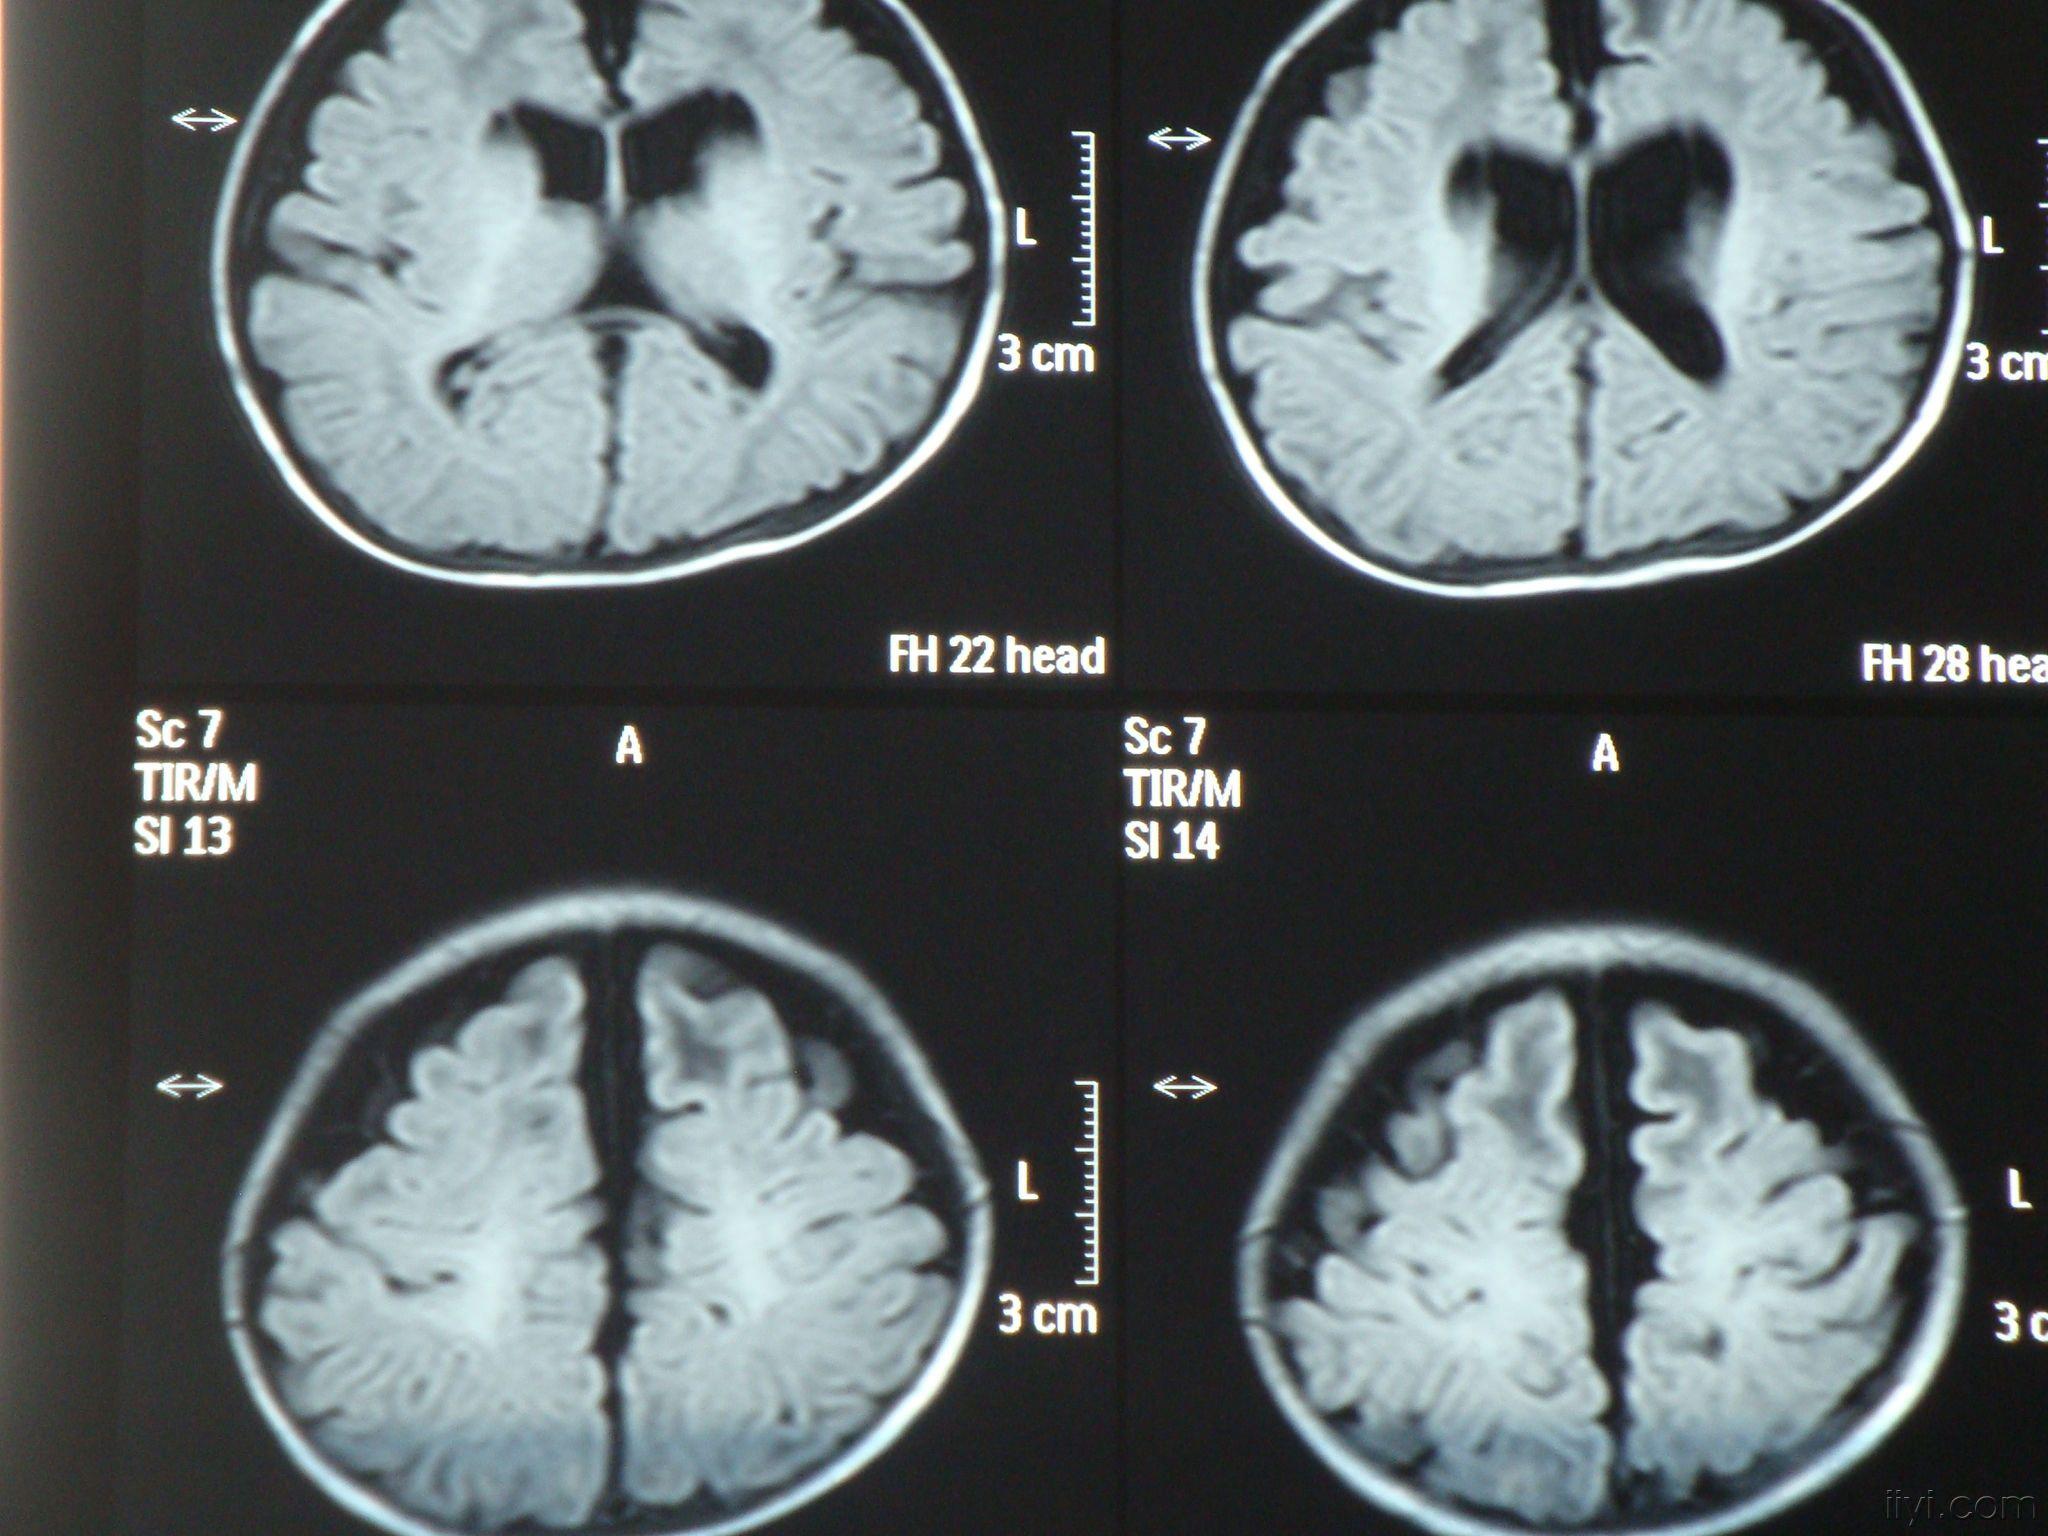

脑萎缩核磁

脑萎缩核磁,

脑萎缩病灶,逐渐到后期病变出现脑萎缩.

图一:mri显示小脑萎缩